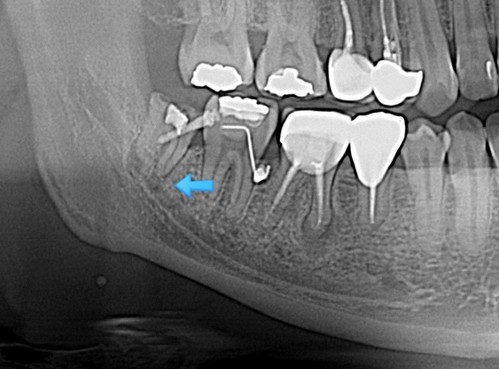

그리고 한 달이 더 흐른 후 x-ray를 확인하며 너무 행복했다.. 노력이 헛되지 않았으니

수술날짜를 잡고 나머지 뿌리도 깨끗하게 발치완료~

교정력을 주어 열심히 당기기 한 달 별다른 위치변화가 보이지 않아서 좀 답답하다...